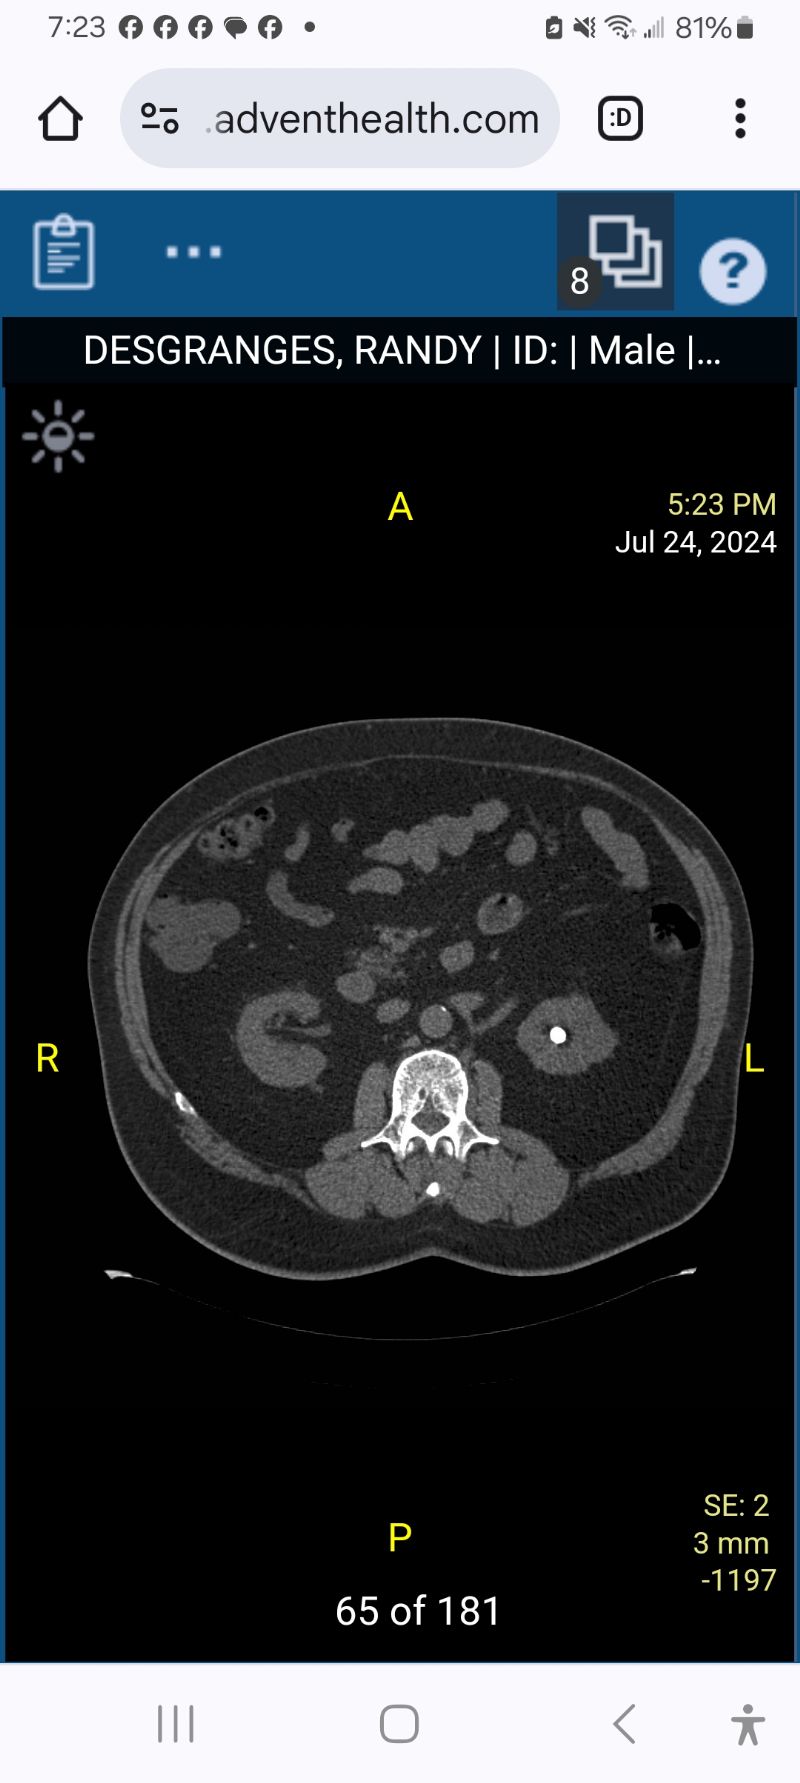

I had a procedure to remove 4 large kidney stones from my left kidney. They used a laser to break them up and suction out the pieces. I have a stint in my kidney now to ease in drainage if anything is left behind. Next Friday I get to do it again with my right kidney.

The CT scan shows one of the stones that is 1cm (10mm).

That image shows a bright stone my X-ray the stone was not bright at all I could hardly tell there was anything there.